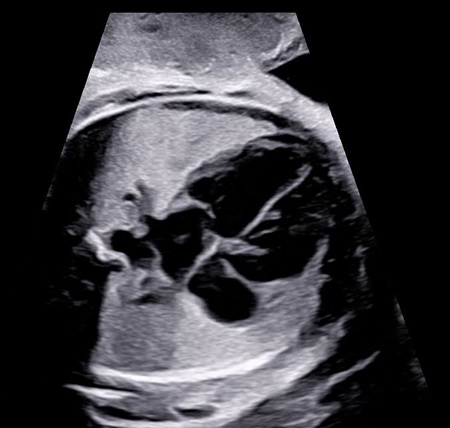

Le 5D CNS+™ est un module qui permet de générer et de reconstruire 9 plans de coupe automatiquement à partir d'une acquisition volumique sur le cerveau fœtal. Les calipers sont positionnés automatiquement par l'échographe à la demande de l'utilisateur.

5D Heart™ est un outil intelligent permettant d’établir un diagnostic cardiaque fiable grâce à la visualisation des 9 coupes essentielles, recommandées par les sociétés internationales. Couplé à l’analyse des échanges vasculaires cardiaques, il rend l’examen du cœur plus intuitif indépendamment de la position du fœtus.